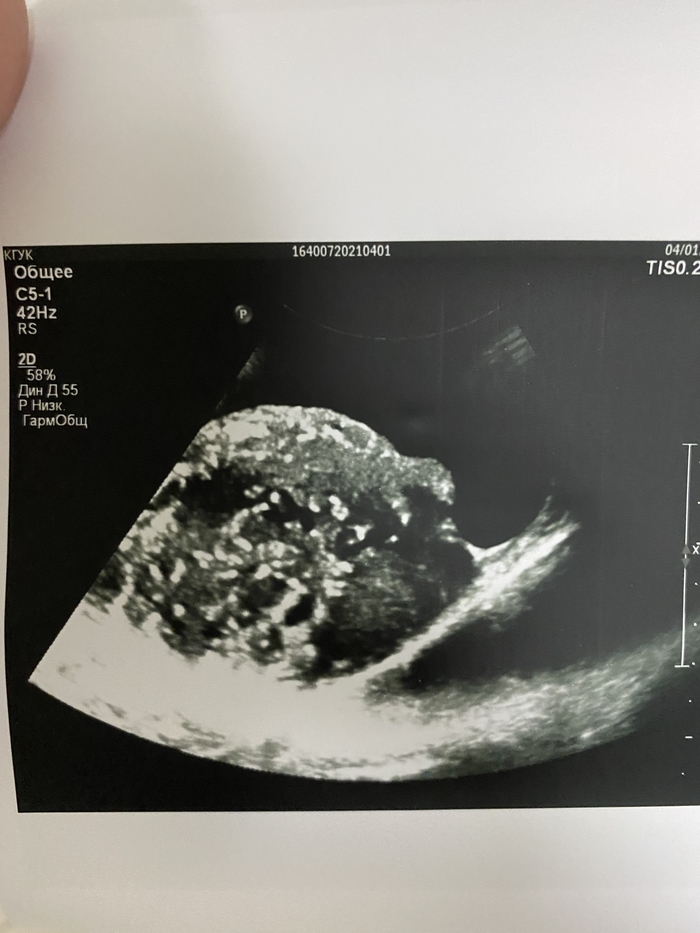

Было назначено УЗ-исследование вен нижних конечностей, которое исключило тромбоз, но при попытке вывести подвздошные сосуды, в полости малого таза оказалось случайной находкой объёмное образование, которое представляет из себя конгломерат из петель кишечника и предстательной железы.

Крайне сложно напугать врача, пусть и с не очень большим стажем в 10 лет. Но собственно, что ожидала, то и увидела. Увеличенная мошонка, несколько покрасневшая, но когда поставила датчик, то мне прям стало почти физически больно.

Не получается у меня прикрепить видео ультразвуковой картинки, как выглядят яички при раке.

Оставлю так и попробую вставить фото.

На фоне гидроцеле (скопления жидкости в мошонке) визуализируются идентичные друг другу изменённые яички и придатки, слабо дифференцируется ткань яичек, кровоток сохранен.